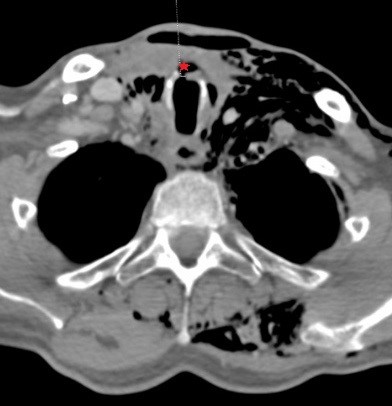

Se realiza tomografía computarizada (TC) cervical y de tórax superior con contraste intravenoso y adquisición de imágenes en fase venosa en inspiración y en Valsalva. En ella se aprecia enfisema de partes blandas que se distribuye disecando los espacios cervicales desde el espacio masticador izquierdo extendiéndose a la región submandibular bilateral, cervical posterior y al hemitórax y que también asocia componente de neumomediastino y de neumopericardio. Existe una imagen sugestiva de pequeña solución de continuidad (2-3 mm) en la cara anterior traqueal entre el cartílago cricoides y el primer anillo traqueal; que coincide con el trayecto de la traqueostomía previa (ver imagen 2). Todos estos hallazgos radiológicos son compatibles con pequeña fístula traqueal; aparte presenta cambios postquirúrgicos de tiroidectomía total y no se aprecian colecciones definidas.

Imagen 2: Solución de continuidad (2-3 mm) en la cara anterior traqueal entre el cartílago cricoides y el primer anillo traqueal (ver asterisco) con extenso enfisema subcutáneo y burbuja adyacente.